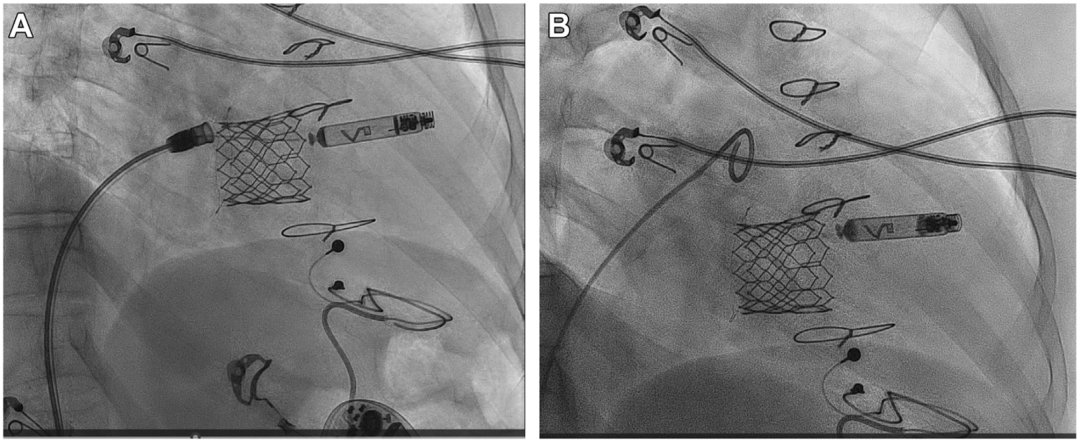

• 缓慢回撤保护套筒,同时轻柔推送器械,使其与心肌充分接触;Mapping测试参数后,根据器械体部的V形标记判断,顺时针旋入1.5圈后,将起搏器进入对接栓模式,损伤电流及参数测试理想:感知6.0mV,阻抗550Ω,阈值0.75V@0.4ms;随后释放起搏器,从传送鞘管中撤出输送系统(图2);

图2 AVEIR VR处于对接栓模式及最终释放影像AVEIR AR植入过程